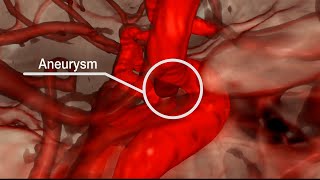

Mayo Clinic Minute: What’s an aneurysm? video

Mayo Clinic Minute: What’s an aneurysm?

Mayo Clinic Minute: What’s an aneurysm?